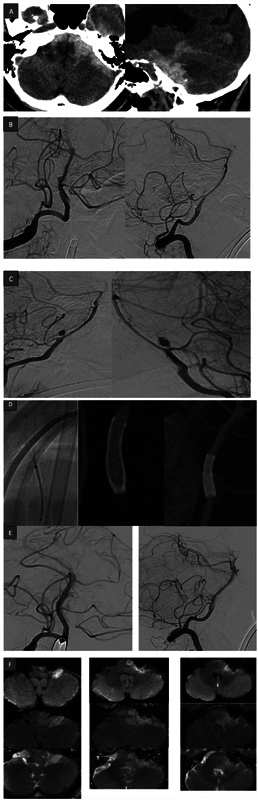

Objectives Subarachnoid hemorrhage (SAH) resulting from rupture of basilar artery perforator aneurysm (BAPA) is a neurological rarity. With increased awareness and advancements in imaging modalities, they are now more frequently detected. However, concerns regarding their suboptimal treatment and lack of proper analysis still exist. We are hereby reporting our experience of treating this entity in a small cohort. Materials and Methods  It is a retrospective study of all the cases of SAH resulting from rupture of BAPA, which were treated by the same surgical team. Demographic data, treatment characteristics, and follow-up data of our cases along with published literature were studied. Results  Our cohort comprised of five patients (mean age 55 years). Three cases were treated with flow diverter alone and the rest underwent flow diverter and overlapping stent placement. Initial diagnostic cerebral angiography (digital subtraction angiography) was negative in three of them. There was one mortality and favorable outcome was encountered in the remaining cases. All of them demonstrated complete occlusion of the aneurysm in follow-up. Conclusion  Following treatment, all the cases demonstrated complete angiographic occlusion of the aneurysm. In available literature, studies have small sample sizes. Future randomized studies in a larger cohort and proper reporting and analysis of outcomes will help us formulating a treatment protocol for BAPA.

Abstract Image